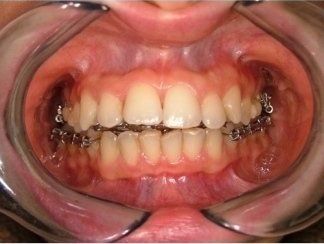

L'idea innovativa di applicare delle maniglie (brackets) sul lato interno dei denti, rivolto alla lingua anziché sul lato esterno rivolto al labbro ed esposto al sorriso, ha fatto sì che questa tecnica venisse denominata “linguale".

I risultati dell’ortodonzia linguale sono gli stessi di quelli ottenuti con gli apparecchi tradizionali, ma a causa della maggiore difficoltà che possono incontrare gli operatori questa tecnica è ancora usata solo da pochi specialisti in Italia e nel mondo.